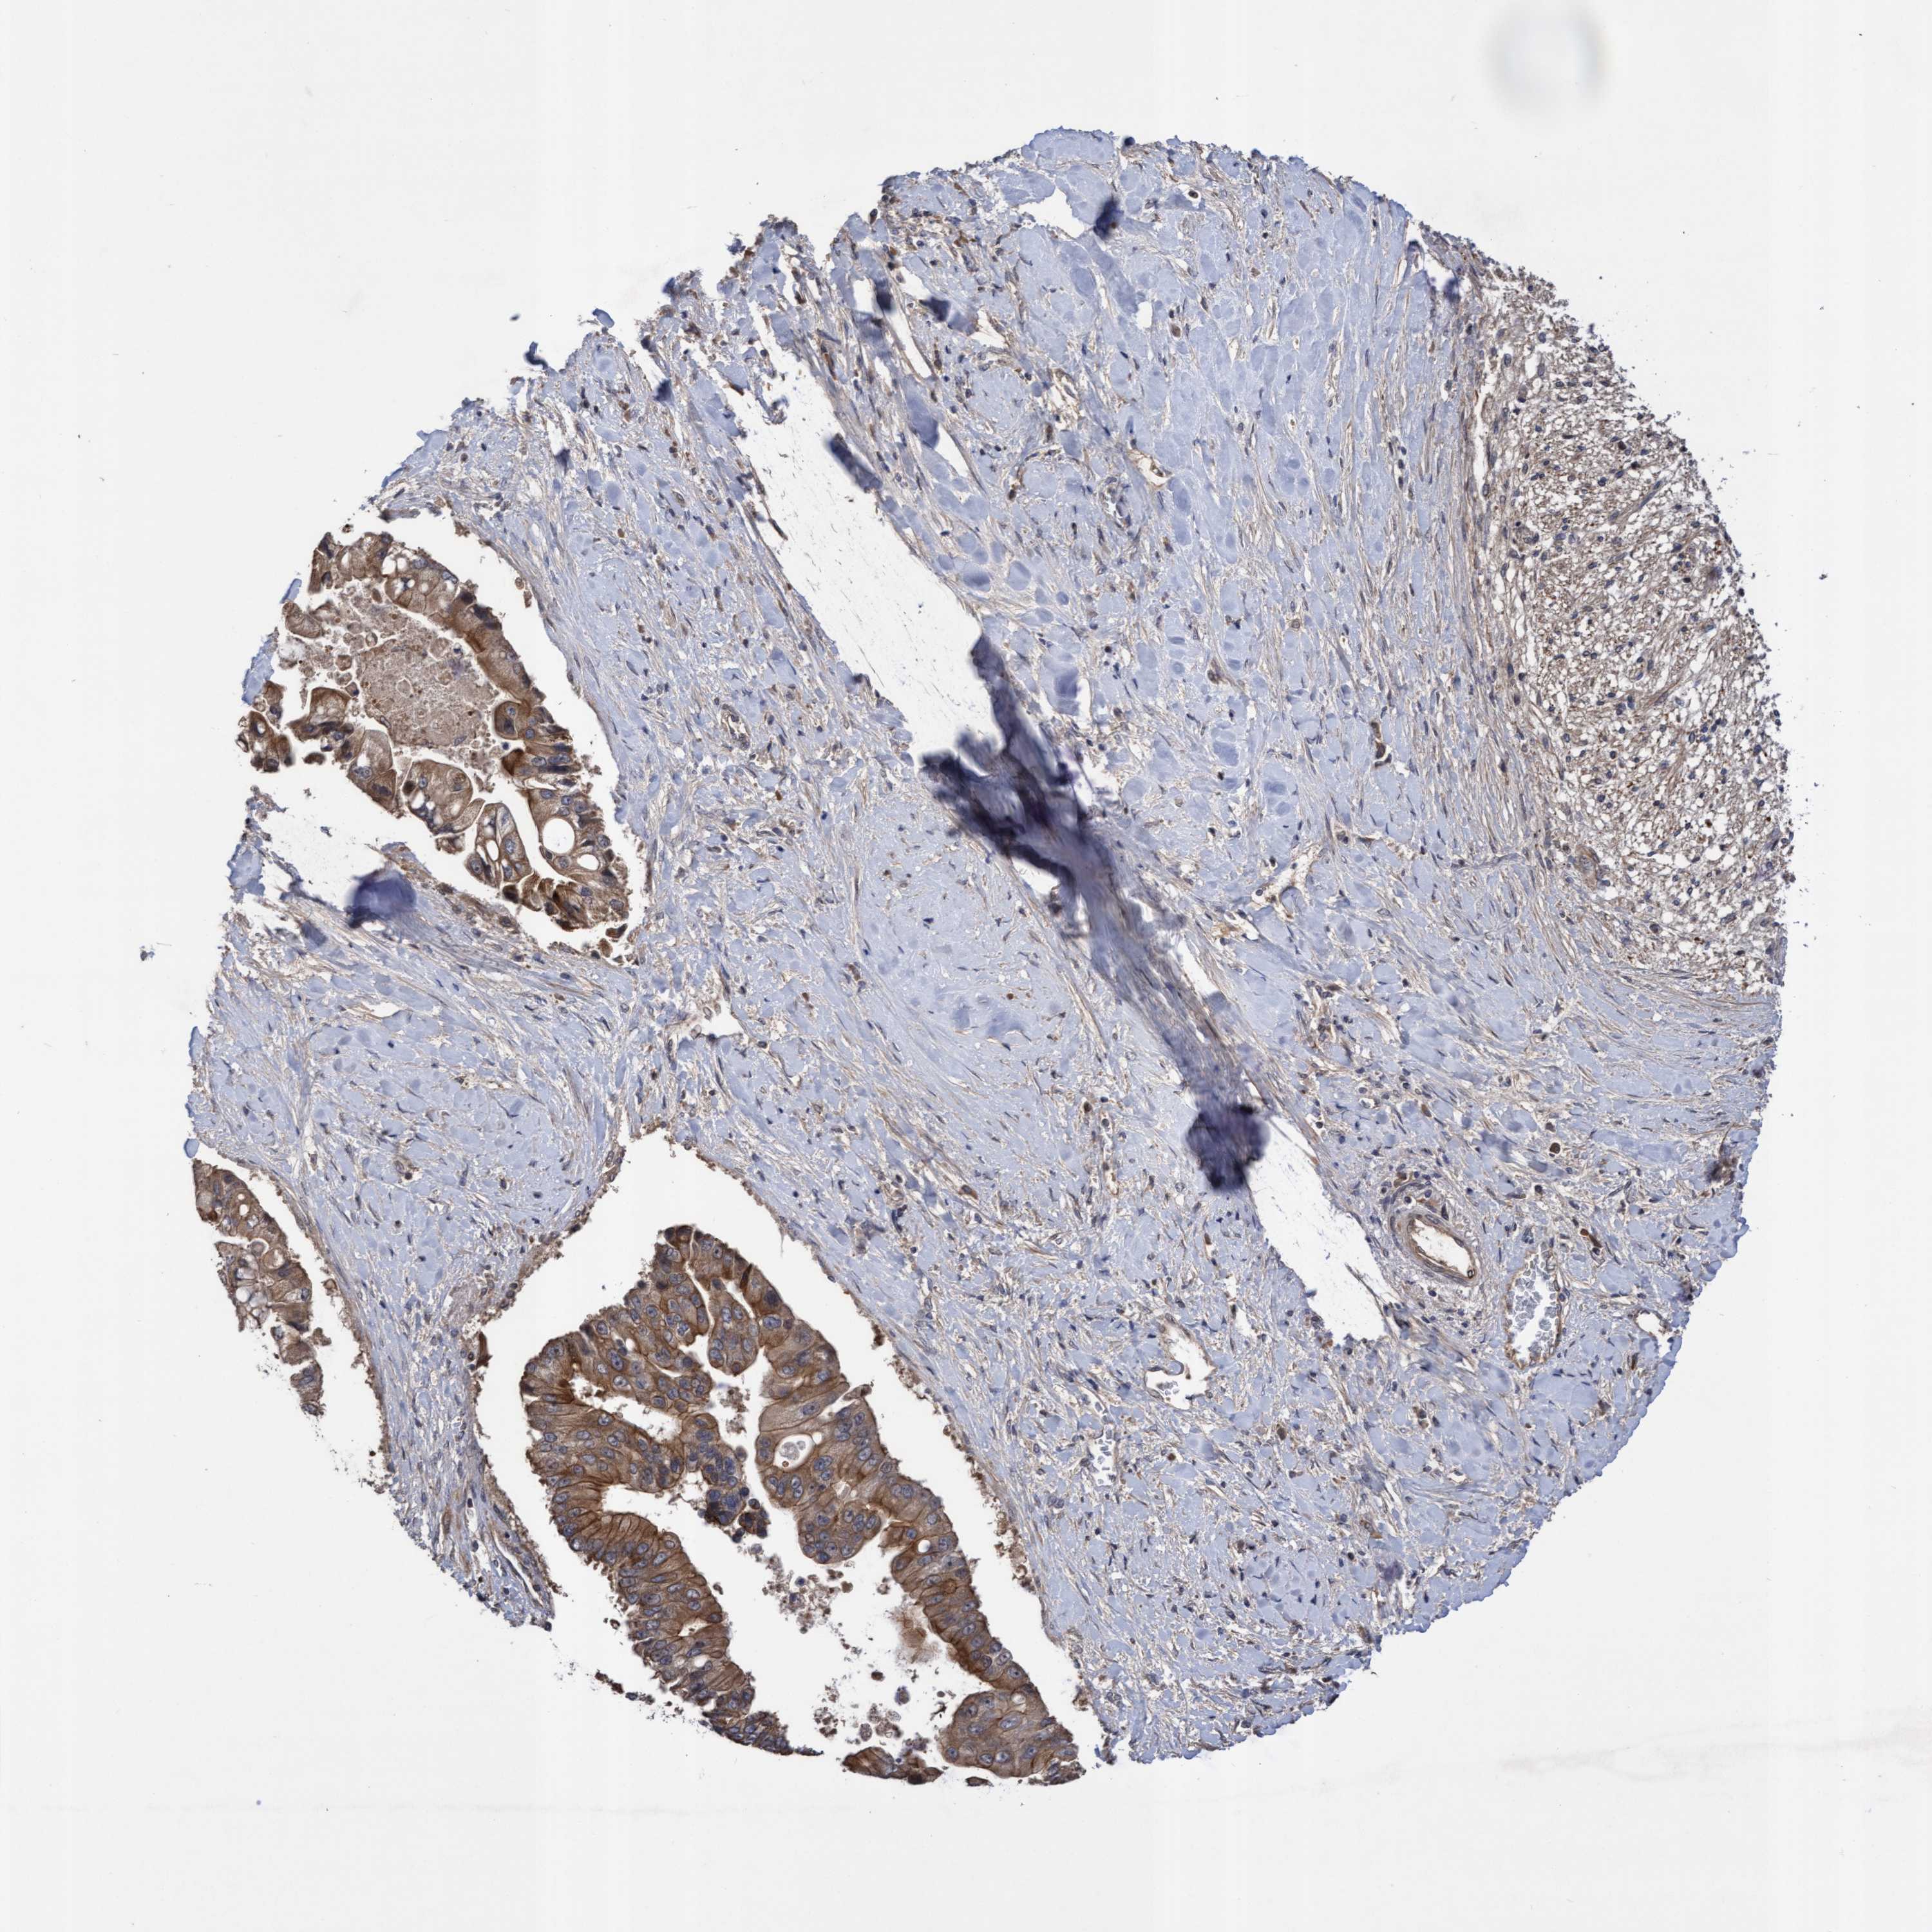

LIVER CANCER - Protein expressioni

A mouse-over function shows sample information and annotation data. Click on an image to view it in a full screen mode. Samples can be filtered based on level of antibody staining by selecting one or several of the following categories: high, medium, low and not detected. The assay and annotation is described here.

Note that samples used for immunohistochemistry by the Human Protein Atlas do not correspond to samples in the TCGA dataset.

Antibody stainingi

Antibody staining in the annotated cell types in the current human tissue is reported as not detected, low, medium, or high, based on conventional immunohistochemistry profiling in selected tissues. This score is based on the combination of the staining intensity and fraction of stained cells.

Each image is clickable and will lead to virtual microscopy that enables deeper exploration of all samples and also displays staining intensity scores, fraction scores and subcellular localization as well as patient and tissue information for each sample.

Antibody HPA019033

Antibody HPA019167

Staining

High

Medium

Low

Not detected

Intensity

Strong

Moderate

Weak

Negative

Quantity

>75%

75%-25%

<25%

None

Location

Nuclear

Cytoplasmic/membranous

Cytoplasmic/membranous,nuclear

Cholangiocarcinoma

Carcinoma, Hepatocellular, NOS